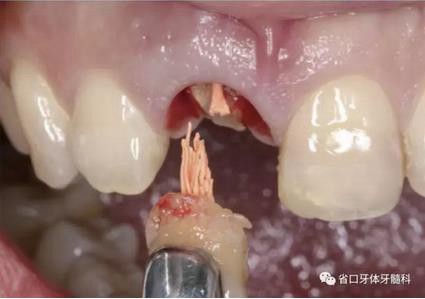

圖5 微創(chuàng)拔牙

圖7 根尖區(qū)肉芽

(1)微創(chuàng)拔牙及即刻種植:術(shù)前拍攝口內(nèi)照及實(shí)施牙周基礎(chǔ)治療。常 規(guī)消毒鋪巾阿替卡因局麻下微創(chuàng)拔除上頜右側(cè)中切牙,搔刮拔牙窩及根尖肉 芽組織。探測(cè)牙槽骨唇側(cè)骨壁及鄰面牙槽嵴完整,牙齦無(wú)撕裂。不翻瓣下于上頜右側(cè)中切牙缺隙近遠(yuǎn)中中點(diǎn)的腭側(cè)牙槽骨及根方定位,按照逐級(jí)預(yù)備的原則,緊貼牙槽窩腭側(cè)骨壁制備種植窩洞,植入Zimer®3.7mm×13mm TSV種植體1顆,植入扭矩>35N·cm,以O(shè)sstell測(cè)量種植體的ISQ值為68。 種植體平臺(tái)位于唇側(cè)齦緣中點(diǎn)下3mm,與唇側(cè)骨壁內(nèi)側(cè)面形成的跳躍間 隙約2mm,置入Bio-Oss®細(xì)顆粒骨粉0.25g,上愈合基臺(tái)關(guān)閉創(chuàng)口。術(shù)后 CBCT檢查顯示:種植體利用牙槽窩根方骨質(zhì)固位,緊貼牙槽窩腭側(cè)骨壁, 其唇側(cè)面與牙槽窩唇側(cè)骨壁的內(nèi)側(cè)面所形成的跳躍間隙(約2mm)可見(jiàn)顆 粒狀顯影物充填。牙槽窩的唇側(cè)骨壁及唇側(cè)倒凹無(wú)缺損穿孔。